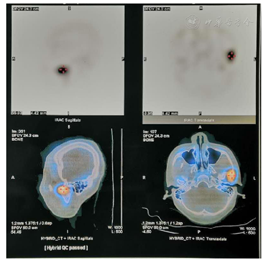

治疗前Tm99核素检查(图7):右:左=1:1.76,提示左髁突异常增生

本病例患者在此次求治3年前曾于外院行"左侧MEDPOR假体植入+颏成形术",以期通过改变下颌体部形态并摆正颏部获得美观改善。此种方法创伤虽小,但并未针对病因治疗,因而无法阻止髁突增生活跃期带来的疾病进行性加重。临床工作中双侧髁突骨盐代谢比作是评价髁突增生程度的客观指标,以患侧代谢超过对侧的17%作为判断是否切除患侧髁突的标准。本病例中该指标为1:1.76,远远大于17%的标准,代表患侧髁突增生活跃。从CBCT来看,髁头及髁颈部可见囊性变区域,为增生代谢活跃导致。